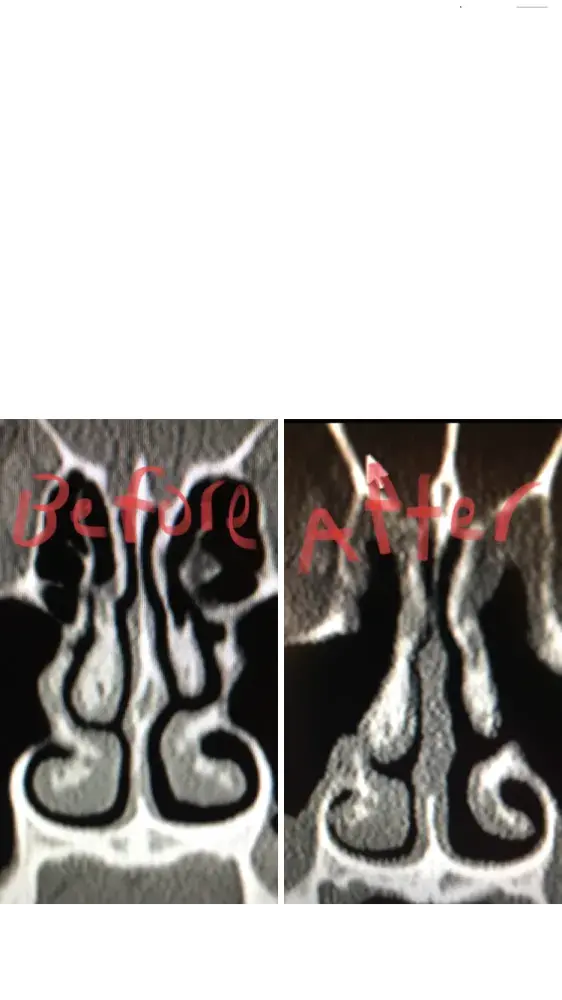

For people reading this, I have included x-ray images of the inside of my nose, before and after my surgery with him. As you can see from these images, my nasal airway was equally open on both sides, before surgery, and the septoplasty didn't need to be done. By performing it, he severely narrowed the right side of my nasal airway.

Dr Raviv performed two surgeries on me: endoscopic sinus surgery (where they widen the sinus passages), and septoplasty (where they straighten the septum). The septoplasty, however was completely unnecessary, and severely narrowed the right side of my nasal airway. For people reading this, I have included x-ray images of my sinuses, before and after my surgery with Dr. Raviv. As you can see from the surgery, my airway was much more open, and equal on both sides, before my surgery with him.